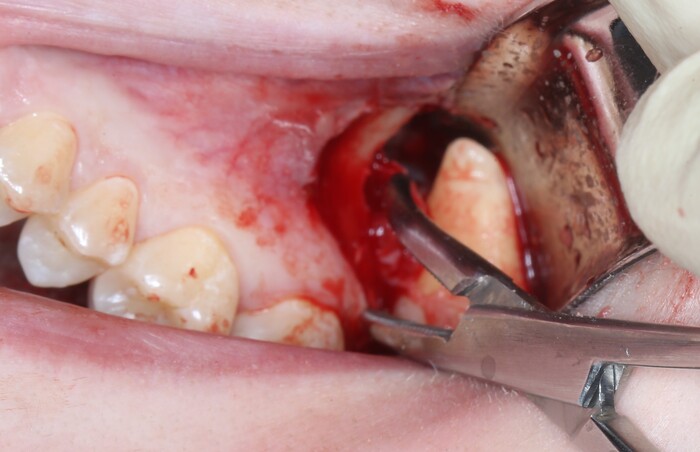

Я сделал анестезию, разрез и отслоил слизисто-надкостнечный лоскут:

Добрался до кости и при помощи специального прямого наконечника и шаровидного бора сделал окошко в проекции верхнечелюстной пазухи и удаляемого зуба мудрости:

Вооон там сверху уже можно увидеть жевательную поверхность зуба (белого цвета).

Понял, что окошко маловато. Немного «расширяемся»:

и начинаем подтягивать зуб при помощи элеватора:

Вот и он «красавчик». Берем зажим и хватаем эту мразоту за хвост, точнее за фолликул и извлекаем: